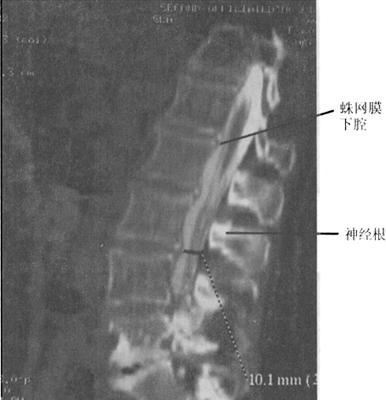

CT与MR出现以来,脊髓造影已不再常规使用。但在复杂的脊柱损伤CT扫描中,无法显示硬膜囊内结构,使用水溶性非离子型鞘内造影剂进行脊髓造影后CT扫描(CTM)扩展了CT在脊髓损伤中的应用(图7-11)。

图7-11 脊髓造影后多排螺旋CT扫描矢状面重建,可区分脊髓、神经根。蛛网膜下腔充满造影剂呈高密度,而脊髓、神经根呈中等密度

传统的脊柱造影需要病人配合医生转动体位来控制造影剂在椎管里的流动,而对脊髓损伤的病人,这可能是致命的危险,俯卧位似乎比侧卧位及仰卧位更易导致椎骨脱位。CrM对神经系统损伤病人的术前评估更有价值。当MR成像更普及时,脊髓X线摄影术和CTM的运用将逐步减少。

当脊髓、马尾神经被软组织压迫或怀疑硬脊膜撕裂时,CTM扫描就显得特别有用。一般来说,鞘内注射造影剂是通过C1~C2穿刺,以减少搬动病人所带来的潜在损伤。CTM的优点在于:①脊髓更好地显影;②提高软组织损伤压迫脊髓的诊断显示率,例如椎间盘突出或硬膜外血肿;③脊髓神经根的硬膜撕裂的诊断。CTM较之传统X线体层摄影、脊髓造影和CT平扫在脊椎骨折损伤的神经定位方面有较大的优越性。脊髓压迫可以在X线脊髓造影中显示,但在CTM中显示更清楚直观。在严重压迫的情况下,髓内创伤的诊断是非常困难的。硬膜外不同程度的压迫可导致脊髓不同程度的破裂。当造影剂充盈硬膜囊时,严重的脊髓损伤可出现脊髓缺损的征象。硬膜撕裂可导致造影剂外渗至硬膜外间隙。尽管撕裂的硬膜可自愈,但识别硬膜撕裂也是很重要的,因为撕裂可能导致多种后遗症,如脑膜炎、神经根内陷,脑脊膜突出或延迟神经损伤。CTM在全脊髓损伤病人诊断中的作用仍存在争议。